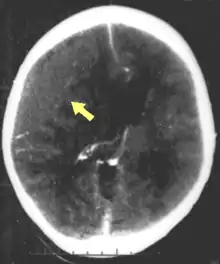

Hematomas, also focal lesions, are collections of blood in or around the brain that can result from hemorrhage.[11] Intracerebral hemorrhage, with bleeding in the brain tissue itself, is an intra-axial lesion. Extra-axial lesions include epidural hematoma, subdural hematoma, subarachnoid hemorrhage, and intraventricular hemorrhage.[38] Epidural hematoma involves bleeding into the area between the skull and the dura mater, the outermost of the three membranes surrounding the brain.[11] In subdural hematoma, bleeding occurs between the dura and the arachnoid mater.[23] Subarachnoid hemorrhage involves bleeding into the space between the arachnoid membrane and the pia mater.[23] Intraventricular hemorrhage occurs when there is bleeding in the ventricles.[38]

Movement disorders that may develop after TBI include tremor, ataxia (uncoordinated muscle movements), spasticity (muscle contractions are overactive), myoclonus (shock-like contractions of muscles), and loss of movement range and control (in particular with a loss of movement repertoire).[89][147] The risk of post-traumatic seizures increases with severity of trauma (image at right) and is particularly elevated with certain types of brain trauma such as cerebral contusions or hematomas.[138] People with early seizures, those occurring within a week of injury, have an increased risk of post-traumatic epilepsy (recurrent seizures occurring more than a week after the initial trauma).[148] People may lose or experience altered vision, hearing, or smell.[11]